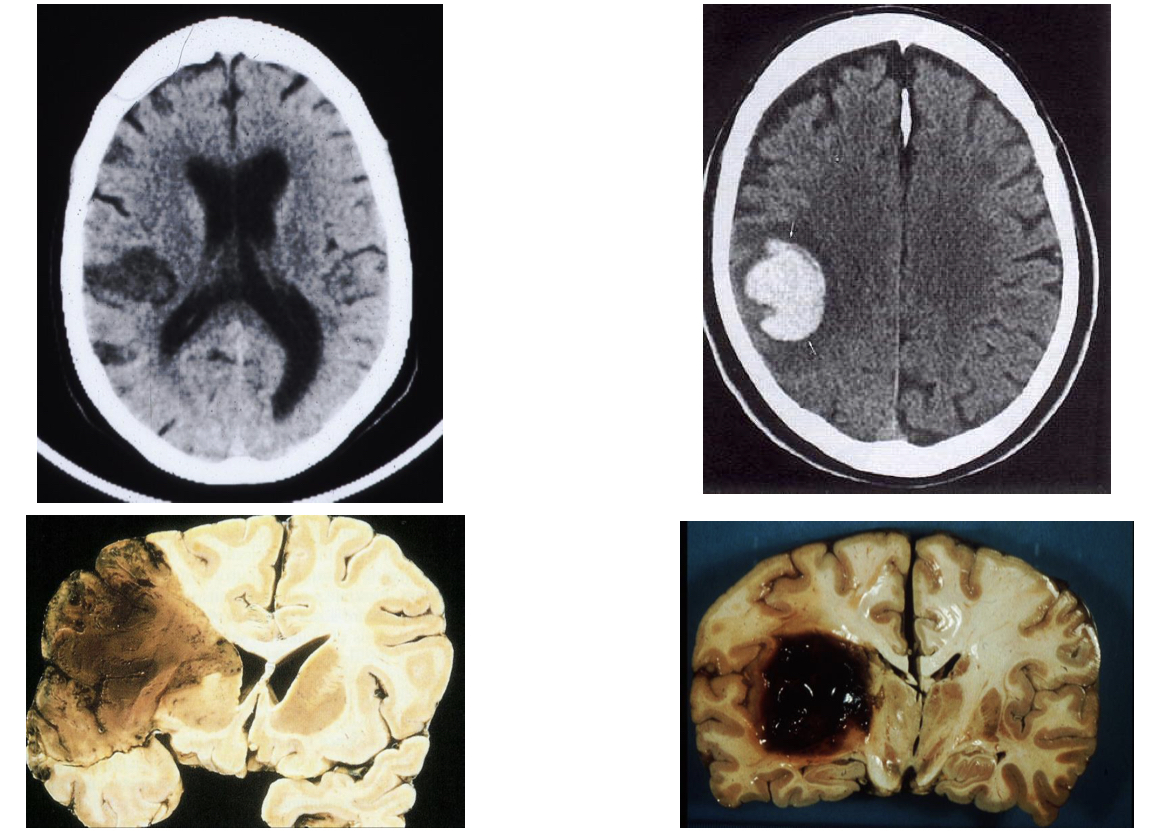

What types of stroke are shown in the images?

A